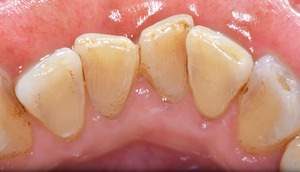

歯石除去

治療前

治療後

| 年齢 | 40歳・男性 |

| 主訴 | 歯石をとりたい |

| 治療内容 | 歯石除去 |

| 治療期間 | 30分 |

| 費用 | 約2,000円 |

| リスク・副作用 | ・歯ぐきの炎症が強いと歯石を取る際に出血することがあります。 ・処置後に歯がしみることがあります。 ・歯と歯の間に隙間ができるので、息が漏れ発音しにくいと感じることがあります。 ・歯ぐきの炎症が軽減すると歯ぐきが引き締まり、歯が長く見えることがあります。 |